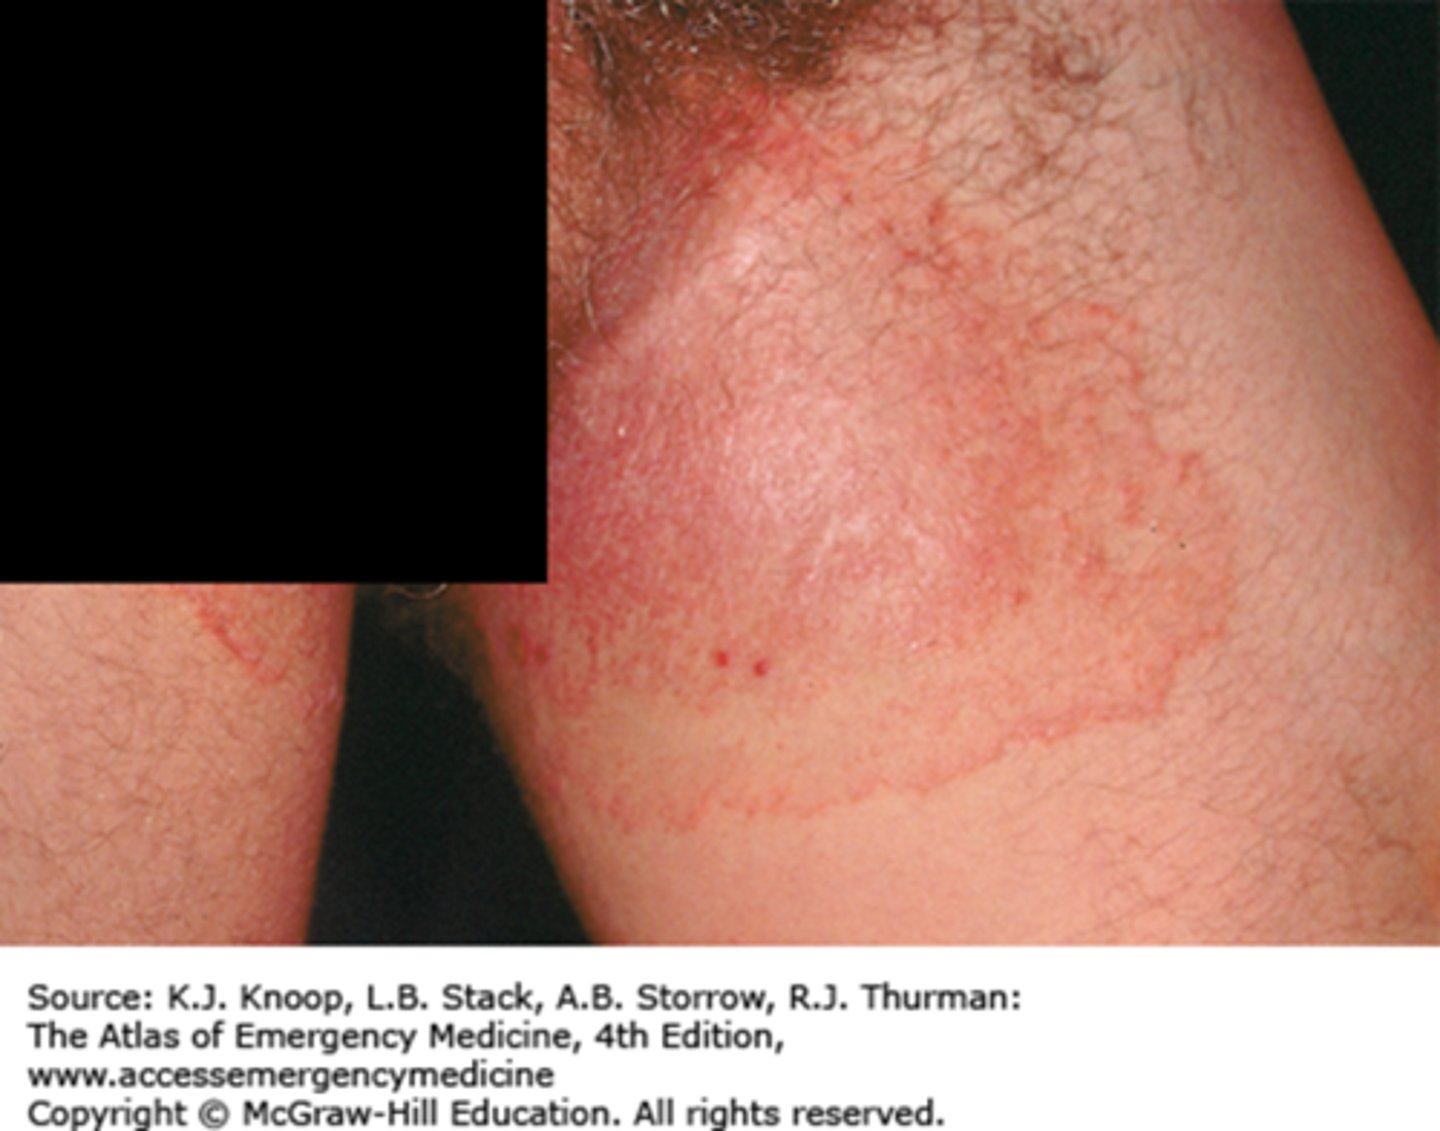

Cellulitis

inflammation of Connective Tissue (most commonly due to bacterial infection)

Tinea Cruis

Ringworm, fungal infection of the groin (jock itch)